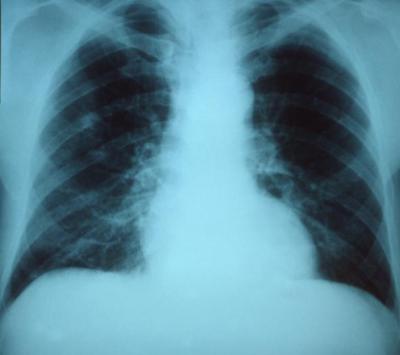

CHAMPAIGN, Ill. — The bacterium Streptococcus pneumoniae – which can cause pneumonia, meningitis, bacteremia and sepsis – likes to share its antibiotic-defeating weaponry with its neighbors. Individual cells can pass resistance genes to one another through a process called horizontal gene transfer, or by "transformation," the uptake of DNA from the environment.